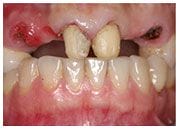

治療前